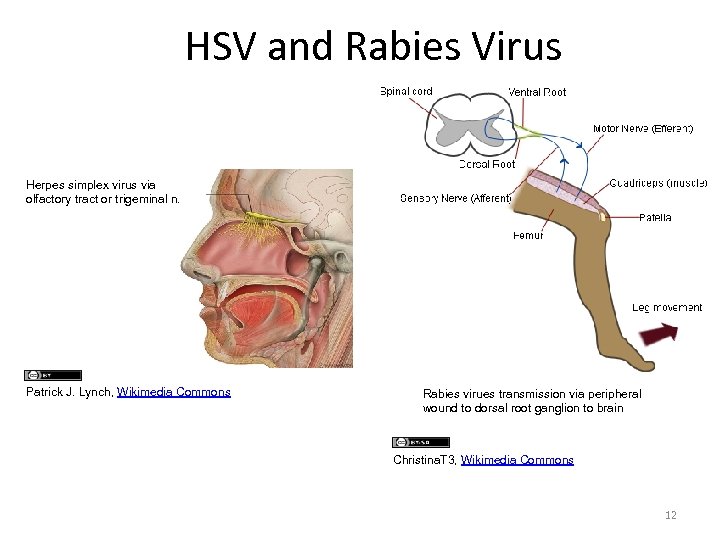

HSV and Rabies Virus Herpes simplex virus via olfactory tract or trigeminal n. Patrick J. Lynch, Wikimedia Commons Rabies virues transmission via peripheral wound to dorsal root ganglion to brain Christina. T 3, Wikimedia Commons 12